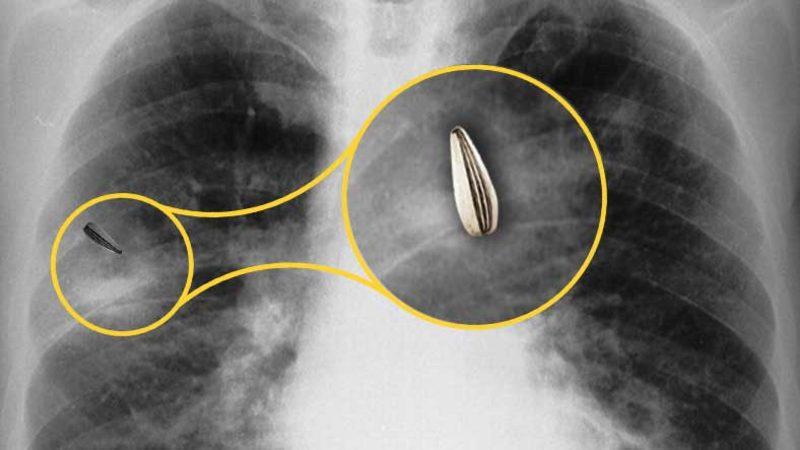

Durumun hemen fark edilmesi veya belirtilerin çoğalması sonucunda hekime başvurmak oldukça önemlidir. Yiyeceğin akciğerde kalması enfeksiyon gibi bir dizi sorunlara yol açabileceğinden çıkarılması için gerekli yöntemlerin izlenmesi gerekir. Teşhis konulması için ise hastanın muayene edilmesinin ardından röntgen veya BT çekilebilir. Ancak akciğer grafisi normal olsa bile semptomlardan dolayı şüphe devam ediyorsa bronkoskopi yapılır.

Batı ülkelerindeki çocuklarda aspirasyona yol açan yiyeceklerin başında fıstık gelir. Güneydoğu Asya ve Çin’de kemik parçaları; Yunanistan, Mısır ve Türkiye’de ay çekirdeği ile kabak çekirdeği akciğere kaçan yiyeceklerin ilk sırasındadır.